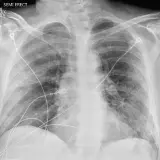

Over 2,100 interactive radiology cases, curated by radiologists for your level of training. Scroll, window, and view cases full screen — just like on PACS. Click linked findings in each writeup to jump straight to them on the image. Cases include sample reports, a focused discussion section, original illustrations, and videos.

Our site includes 3 main courses: Call Preparation, Introduction to Radiology, and Neuro Fellowship.

Call Preparation — our comprehensive curriculum for junior residents preparing for call covering both classic and atypical presentations. Use the call simulator to practice a real call shift — shuffle cases, enter your own preliminary report, and receive constructive AI feedback.

Casos totalmente interativos com as ferramentas que você espera em um PACS — rolagem, ajuste de janela, zoom, movimentação, medidas, ROIs e modo de tela cheia.

Anotações detalhadas destacam os achados principais diretamente nos casos. Clique nos achados vinculados nas descrições dos casos para ir ao local exato no exame.

Exemplos de Laudos

Cada caso inclui um laudo de exemplo breve para ajudar na redação